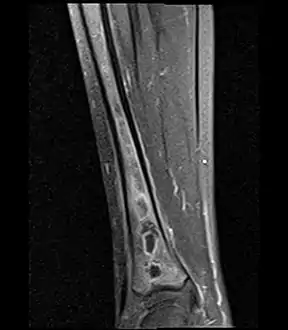

Fat saturated STIR (short tau inversion recovery) image showing hyperintense edema in the calf musculature, marrow edema, and subperiosteal pus. The intramedullary abscess cavity is hyperintense as well. Coronal fat suppressed STIR image showing, bone marrow and subcutaneous edema as well as subperiosteal edema. The thin hypointense rim surrounding the intramedullary collection represents the reactive interface between the abscess and the body's attempt to wall it off.

Coronal fat suppressed STIR image showing, bone marrow and subcutaneous edema as well as subperiosteal edema. The thin hypointense rim surrounding the intramedullary collection represents the reactive interface between the abscess and the body's attempt to wall it off. Axial T1-weighted MRI pre-contrast enhancement showing that the intramedullary collection is T1-hyperintense suggesting proteinaceous viscous fluid consistent with infection.

Axial T1-weighted fat-saturated MRI image following IV gadolinium contrast demonstrating the intramedullary lytic area seen on radiography to be ring enhancing consistent with a purulent fluid collection. Extensive circumferential periosteal enhancement is noted. There is also substantial bone marrow enhancement. Sagittal T1-weighted fat-suppressed post gadolinium image showing the extent of the multiloculated intramedullary abscess.

Sagittal T1-weighted fat-suppressed post gadolinium image showing the extent of the multiloculated intramedullary abscess.